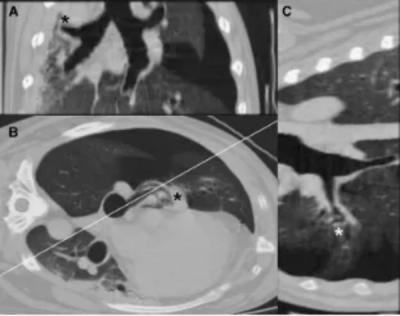

患有右中叶部分扭转的犬仅表现为受累肺叶的肺不张,但支气管位置和气体含量正常(图6)。该犬也存在胸腔积液和气胸。

图 6. 一只6岁混种犬患有右中叶部分扭转。背侧重建CT图像(A),左侧卧位横断图像(B)以及图6B所示平面的斜位重建图像(C)。右中叶(*)塌陷,支气管弯曲,但在重建图像中整个支气管可见且充满气体。